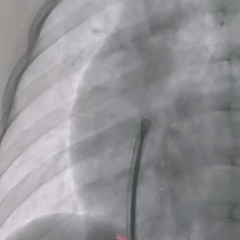

轨道建立

在肺动脉内圈套导丝,建立动静脉轨道

沿导丝送入输送鞘,并将输送鞘压入左心室

右盘展开

DSA下推出右盘,由于缺损隧道较长,为防止右盘展开后被牵拉入隧道内,术中全程保持钢缆张力使左盘稳定贴靠室间隔,再后撤鞘管展开右盘